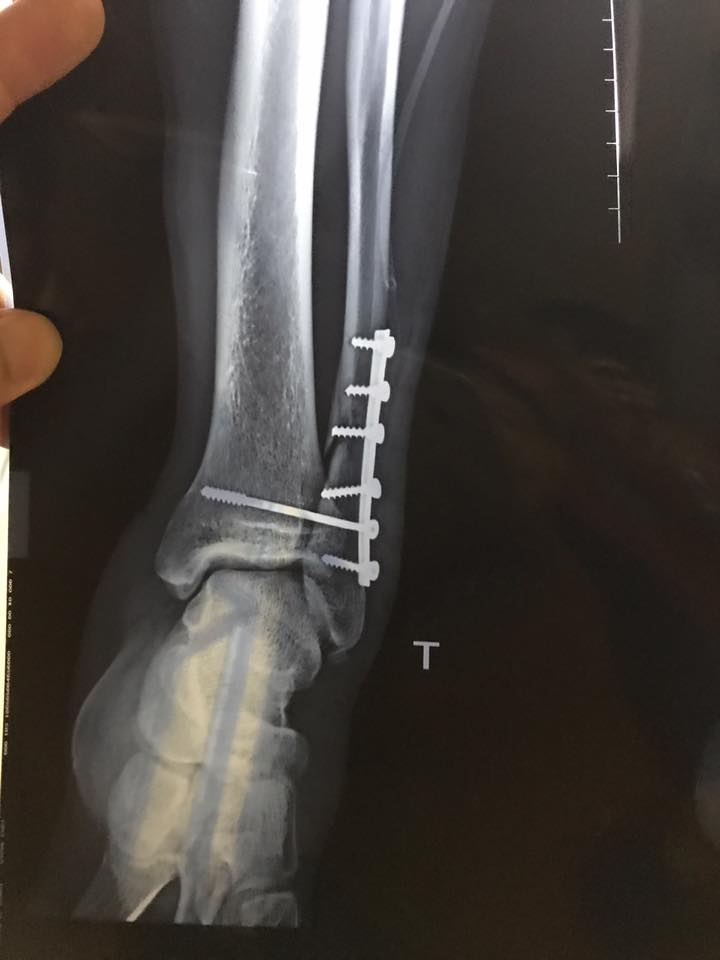

| Phim chụp X-Quang vùng cổ chân trái của Văn Hào. Ảnh: HLV Đặng Phương Nam. |

Thông tin từ CLB Viettel cho hay, kết quả chụp phim sau khi phẫu thuật cho thấy ca mổ xử lý vết thương gãy xương mác của Văn Hào đã thành công.

Hiện tiền đạo sinh năm 1997 được đóng 7 chiếc đinh nhằm cố định vết thương và chuyển về phòng bệnh điều trị tích cực.

Ngoài việc gãy xương, Văn Hào cũng bị bung ổ khớp và các bác sĩ đã tiến hành sắp xếp lại, kết quả cũng tương đối khả quan.